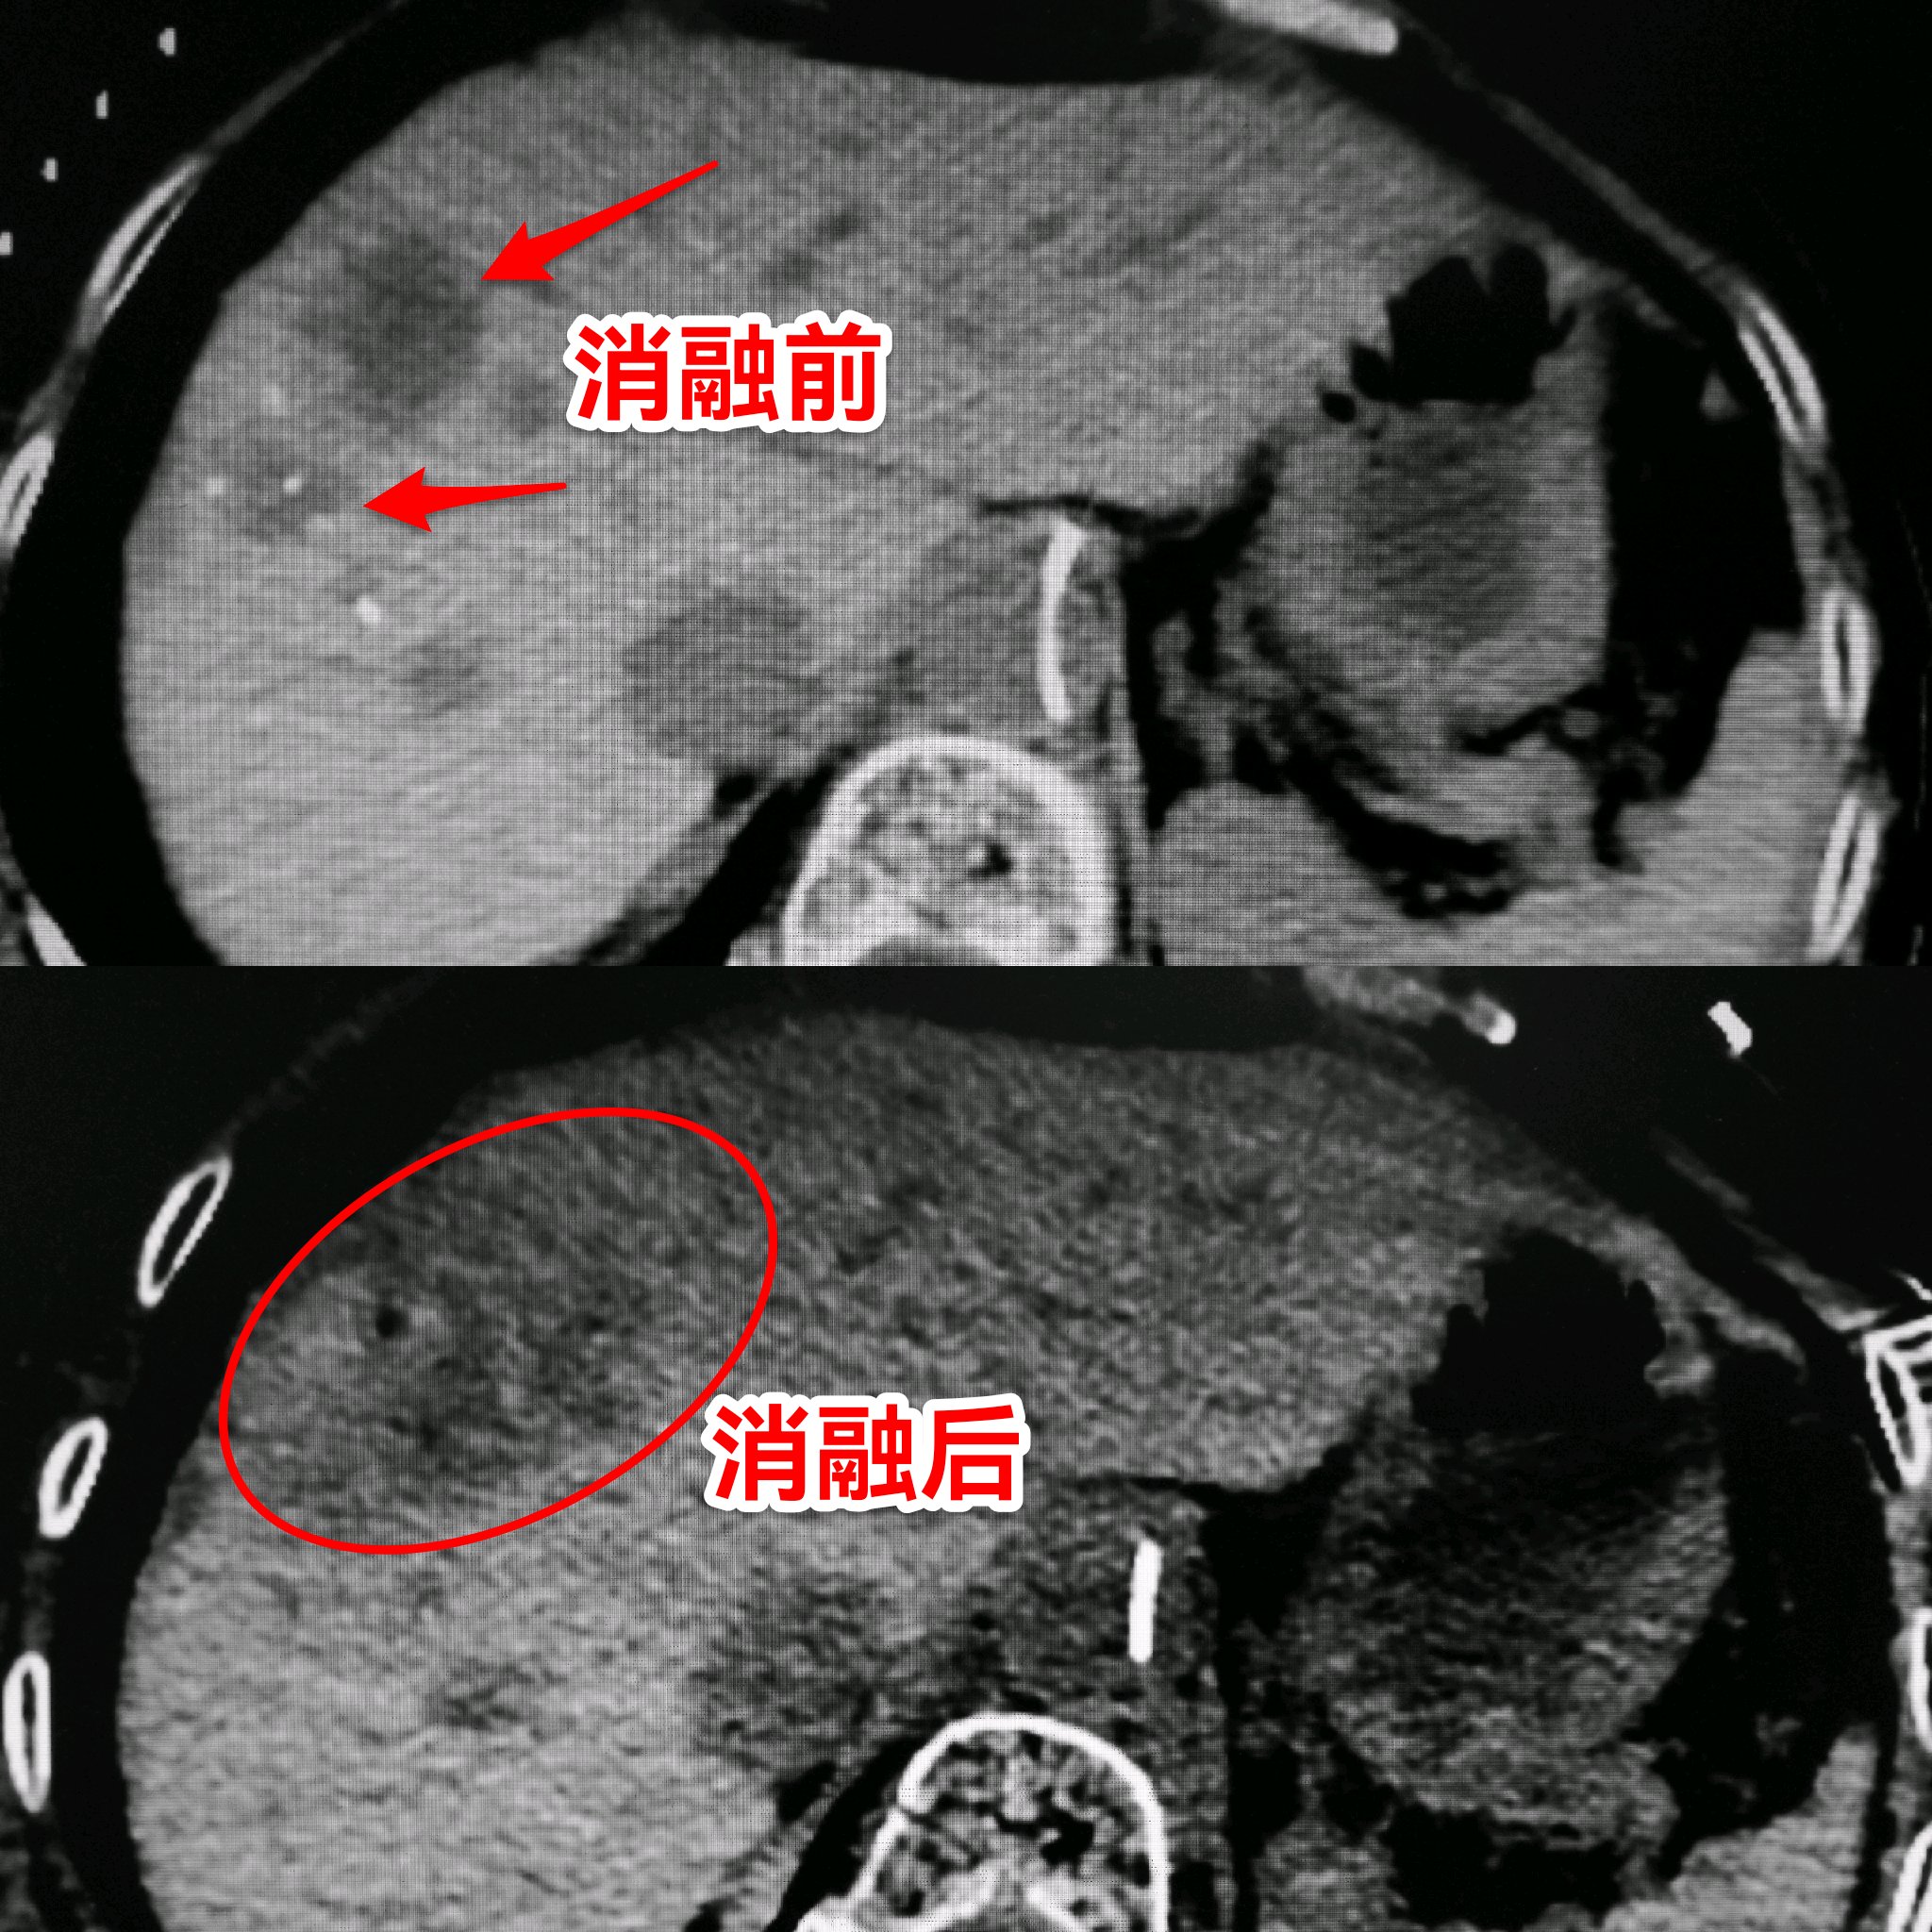

消融前后CT对比:消融后肿瘤组织坏死

例如这个肠癌术后肝转移的病人,结肠没有新发病灶,所以先肝动脉化疗栓塞(机枪扫射)灭活大片肿瘤,再细针穿刺消融(*击狙**步枪点射)灭活三个顽固分子,最大程度的保存正常肝脏,最大程度的消灭肿瘤。伤口只有一个针眼,体现了现代医学 “微创无痛,原装出院” 的理念。